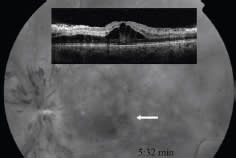

Figure. Fluorescein angiography of an eye with CRVO, with OCT in inset.

COURTESY: TEERAPAT JITTPOONKUSON, MD, PATRICIA M.T. GARCIA, MD, GENNADY LANDA, MD, AND RICHARD B. ROSEN, MD

Examining the cases of 193 patients with RVO and 83 healthy controls, the authors found that the mean platelet volume (MPV) in RVO patients was significantly higher (8.19 ±1.22 femtoliters [fL]) compared to the controls (7.68 ±1.11 fL). However, they detected no difference in absolute platelet counts, indicating larger platelet size in the RVO patients.

Also, MPV was an independent predictor of RVO. The results suggested MPV might contribute to the pathogenesis of RVO, although the limitations of a retrospective study apply.